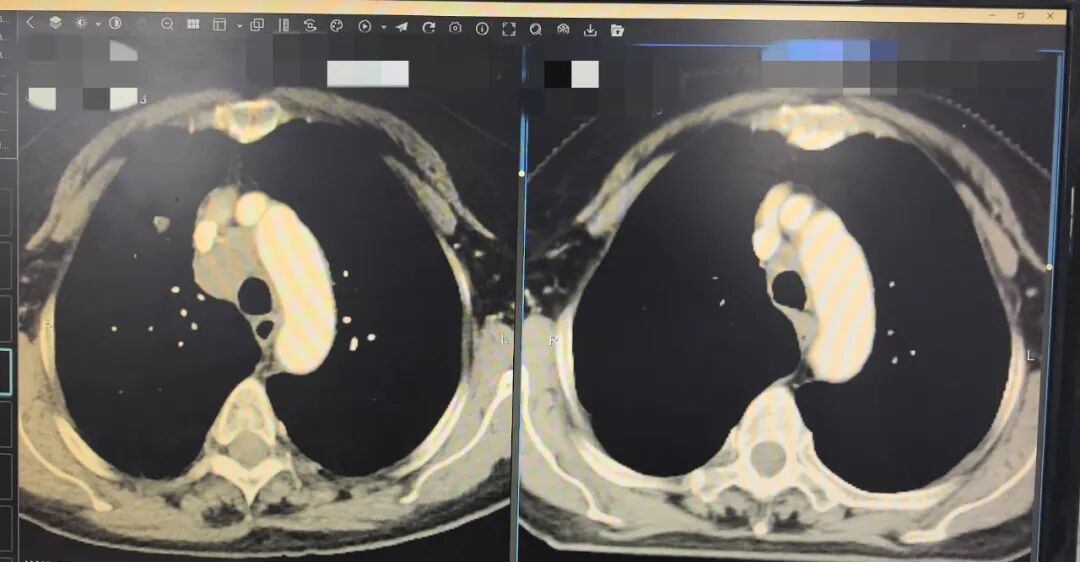

70岁老人小细胞肺癌,放化疗联合免疫治疗稳定病情

病种: 右肺上叶小细胞肺癌(广泛期)

治疗方式: 穿刺活检确诊+ EP方案化疗 + 免疫治疗 + 同步放化疗

2025年12月,患者确诊为右肺上叶占位,伴有纵隔淋巴结转移,病理诊断为小细胞肺癌。该类癌症进展较快,但患者及家属治疗意愿强烈,积极配合。

1. 精准定性:通过穿刺活检明确病理类型。

2. 联合方案:采用国际指南推荐的一线“EP(依托泊苷+顺铂)方案化疗”,联合“卡瑞利珠单抗”免疫治疗。

3. 同步治疗:在化疗期间,根据患者身体状况,同步进行胸部放射治疗。

💡病例小Tips: 小细胞肺癌具有生长快、对放化疗敏感的特点。科室紧跟国内外诊疗指南,采用“免疫+化疗+放疗”相结合的同步综合治疗模式,帮助患者获得了较为良好的近期预后。